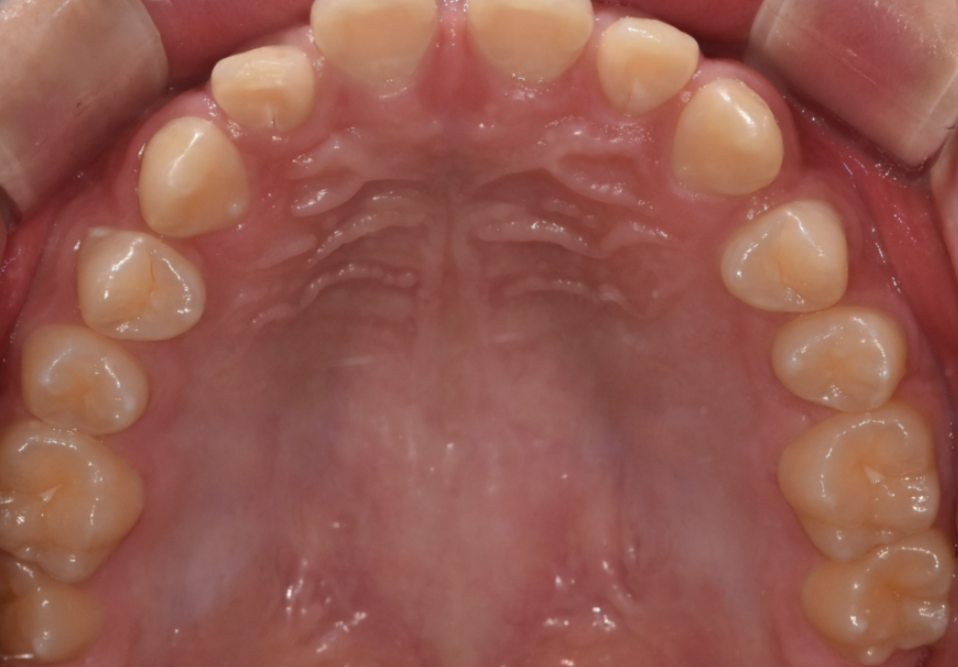

2. 전체 치열, 교합까지 개선할 수 있습니다.

단순히 앞니 공간만 메꾸는 것이 아니라

전체 치열과 교합이 조화롭게 맞춰집니다.

부정 교합을 가지고 있던 환자분들이라던가

어금니도 벌어져 있는 경우 같이 교정 가능하죠.